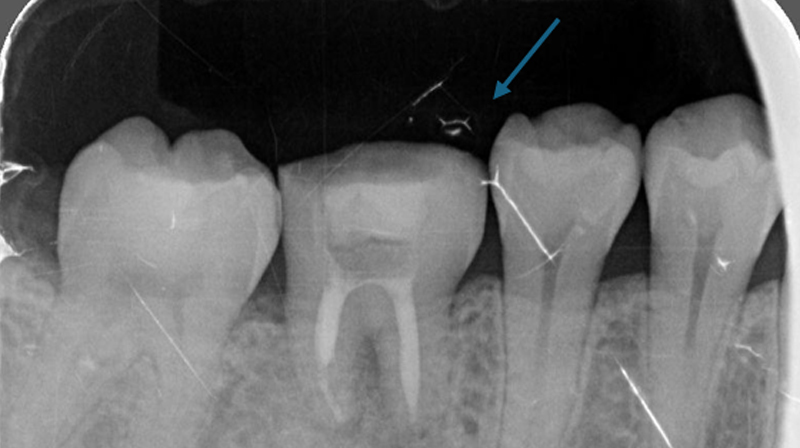

術前

術後

智齒固定